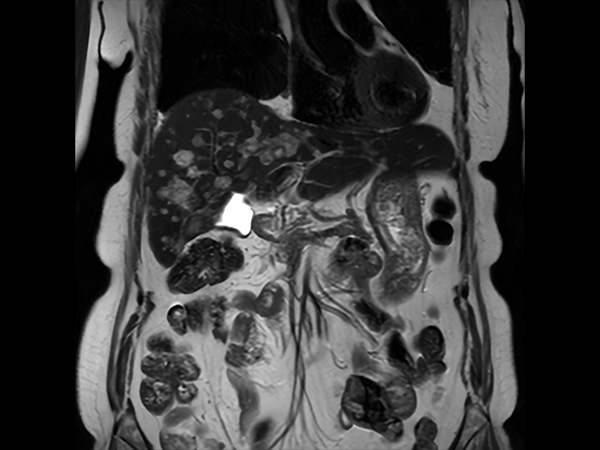

Liver metastasis with SmartSpeed Precise

Coronal T2w SSh